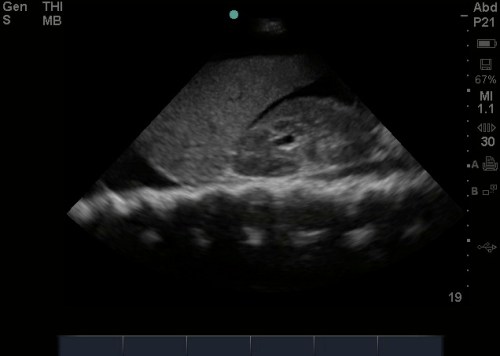

Theoretically, given its dependent anatomical position, one might logically conclude that it should in fact be the most sensitive view to visualize free fluid; unfortunately, the literature has negated this theory – and in fact this can often be the least sensitive view, largely in part of human error, and especially in pelvic fractures.(1,2,4) Anatomically, when we scan the suprapubic area in both transverse and longitudinal planes, there’s a lot that we see –the bladder, bowel, pelvic bones, pelvic organs, and rectum to name a few. This might make it harder for us to visualize free fluid, and separate it out from these other structures. But here’s a few tips to help overcome these limitations. Begin by placing your phased array or curvilinear probe just above the pubic symphysis, aiming inferiorly/caudad into the pelvis.

1. Look through a full bladder. A full bladder – The suprapubic view is visualized using a filled bladder as the acoustic window. Not all trauma patients come in with a full bladder and we will not likely go back to the days when a foley catheter used to be placed in order to fill the bladder for visualization. While we are sure our patients appreciate us not doing this anymore – its important to note, that if your patient has an empty bladder, it is best to hydrate them up with the fluids, and repeat the scan when the bladder is more full.(5) With an empty bladder your ability to adequately discern free fluid is very limited. Mostly due to gas scatter from bowel, inadequate depth adjustments, and inability to discern bowel fluid from free fluid. Click Here for a Video of A Normal Female.

2. Adjust your depth – More often than not, when it is time to scan the suprapubic area, your depth is set too deep from scanning the upper quadrants or cardiac views. We often find that a depth of about 13cm to 16cm optimizes your view. The goal is to have your bladder centered on the screen, to easily visualize the areas surrounding the bladder

3. Adjust your gain – The bladder is a fluid filled structure, and as mentioned before, fluid is the “lover” of ultrasound, allowing structures deep to it to be well visualized, however this often creates an artifact called “posterior acoustic enhancement” that produces a hyperechoic and bright area deep to the bladder. This makes it hard to visualize anechoic or black free fluid. One of the biggest pitfalls is not decreasing your gain to accommodate for this, and limiting your ability to pick up anechoic free fluid.

4. Look everywhere – Unlike in your upper quadrants, free fluid in the pelvic cavity can in fact collect anywhere – anterior, lateral, and posterior to the bladder as well as anterior, lateral, and posterior to the uterus in female patients. This often is dictated by your patient’s position, the lay of the uterus, how full the bladder is, and the size of the prostate to name a few. We suggest looking in four areas –

7. Fan slowly – While fanning is always important in evaluating any region by ultrasound – we cannot stress it enough when evaluating the suprapubic area. It is impressive and often surprising just how much free fluid can “hide” behind and around the many structures present in this region, and not be visualized unless you dedicatedly fan through the area. It is strongly encouraged to view the suprapubic area in 2 planes – horizontally and longitudinally and fan through each section slowly to make sure you don’t miss any free fluid!(3)